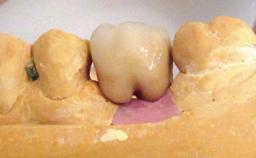

Peri-implant Carcinoma

Oral implants are highly successful and offer long-term benefits, especially in the rehabilitation of edentulous patients or patients with oral defects following ablative tumor surgery (Albrektsson and coworkers 1986), and also after radiation therapy (Schiegnitz and coworkers 2014). With the number of implants placed globally going into the millions, implant dentists have observed some rare adverse events. Although carcinogenesis around implants is an exceedingly rare phenomenon, we recently reported about 15 patients treated for carcinomas adjacent to implants at our clinical department over a period of fifteen years (Moergel and coworkers 2014). The following case represents a patient of this cohort; it discusses possible risk factors and makes suggestions for a recall schedule. A 70-year-old woman was referred to our outpatient department for evaluation of a rapidly growing macroscopic alteration of the mucosa in the left mandible.

Prosthesis Type FDP